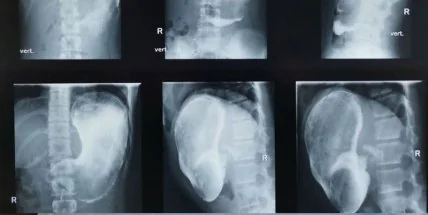

В желудке российской школьницы обнаружили килограммовый ком волос.

"Врачи из детской больницы имени Башляевой спасли жизнь 11-летней девочке, у которой в желудке собрался огромный ком волос — весом в 1 килограмм", - говорится в сообщении.

Врачи во время гастроскопии заметили, что ее желудок заполнен огромным сгустком из непереваренных веществ, пищи и слизи.

В ходе расспросов выяснилось, что девочка имеет вредную привычку обсасывать кончики волос, что и привело к образованию в желудке килограммового кома. Объект мог бы привести к тяжелым последствиям вроде язв или желудочных кровотечений, но врачи смогли вовремя извлечь его.